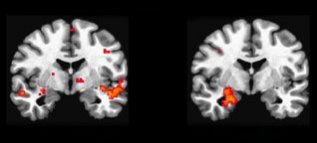

Brains scans show that the brains of teens playing nonviolent games (left) and those of teens playing violent games (right) have different patterns of activity. Those who played violent games showed greater activity in a region of the brain associated wit

The results showed that a part of the brain called the amygdala was especially active in players in the violent-game group, especially when follow-up tasks required them to respond to loaded words, such as “hit” and “kill.” The amygdala prepares the body to fight or flee in high-stress situations.

Moreover, among players in the violent-game group, a part of the brain called the frontal lobe was less active. The frontal lobe helps us stop ourselves from hitting, kicking, and performing other aggressive acts.